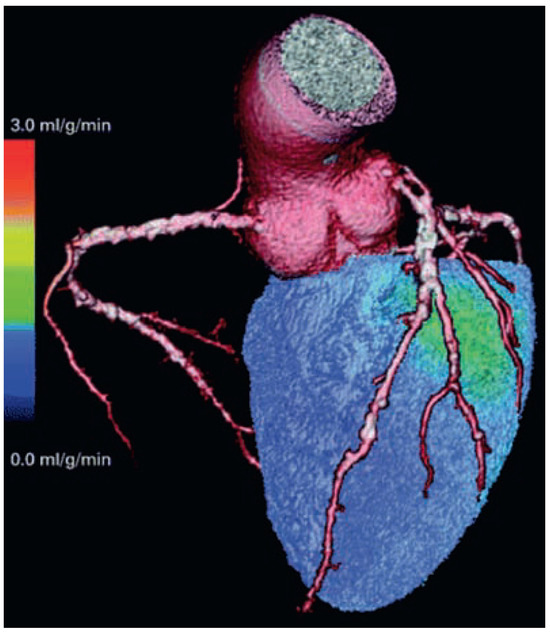

Key Messages: Cardiovascular Imaging 2008

by Michael Zellweger and Christine H. Attenhofer Jost

In cardiovascular imaging, every year there are exciting new findings and advances. This was also obvious at the Swiss Society of Cardiology Meeting 2008 in Berne. In this article we summarise the findings of the most important international and especially national studies in [...] Read more.

In cardiovascular imaging, every year there are exciting new findings and advances. This was also obvious at the Swiss Society of Cardiology Meeting 2008 in Berne. In this article we summarise the findings of the most important international and especially national studies in the fields of echocardiography, cardiac MRI and computed tomography presented at this meeting. Among the total of 279 abstracts, the number of accepted abstracts in the field of cardiac imaging included 14 abstracts especially focussed on echocardiography, 5 on cardiac MRI, 4 on computed tomography and 4 on myocardial perfusion SPECT. In this article, we especially deal with the topics of cardiac resynchronisation, 3D echocardiography, contrast echocardiography, and the most important presentations regarding cardiac MRI, computed tomography, and myocardial perfusion imaging. Increasingly, molecular and hybrid imaging like PET-CT will be part of modern cardiology. This meeting showed that we get closer to the goal of perfect diagnosis and prognosis in cardiology. However, there are some caveats regarding cardiac imaging especially the problem of radiation exposure as well as discussion regarding costs and usefulness of multimodality imaging. Full article

Show Figures

Figure 1